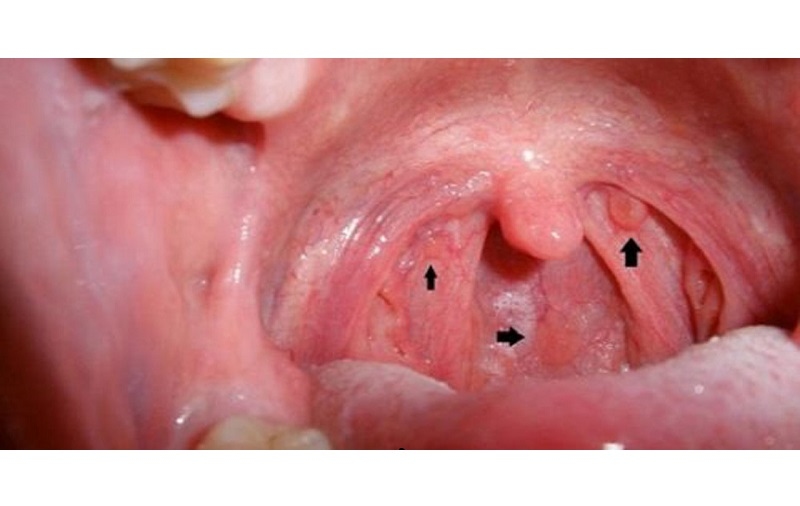

Cấu trúc của họng được chia thành ba phần chính: vòm họng (nằm phía sau khoang mũi), miệng họng (bên dưới vòm họng) và hạ họng (phía dưới miệng họng và phía sau thanh quản).

Ung thư vòm họng là tình trạng phát sinh các tế bào ác tính tại vùng vòm họng – tức khu vực phía sau của khoang mũi. Trong số các dạng tế bào ung thư được tìm thấy, phổ biến nhất là ung thư biểu mô không sừng hóa. Ngoài ra, còn có thể gặp các dạng khác như ung thư biểu mô tế bào gai sừng hóa hoặc ung thư biểu mô tế bào gai dạng đáy, nhưng ít hơn.